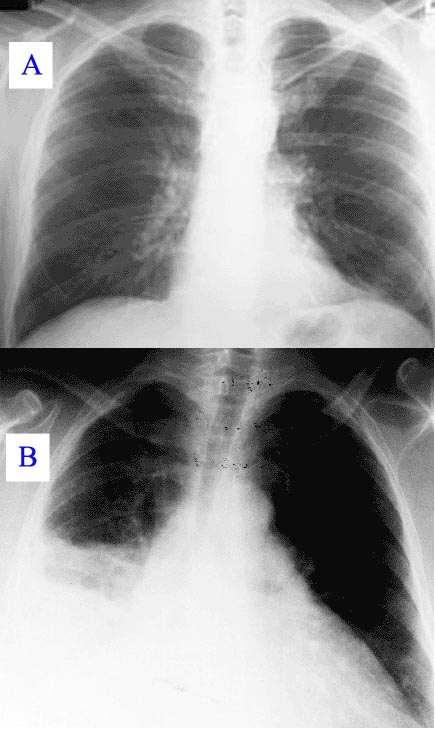

En la gent gran, la manifestació de la pneumònia pot no ser típica. Poden desenvolupar una confusió nova o més greu, o experimentar desequilibris, provocant caigudes. Els infants amb pneumònia poden presentar molts dels símptomes mencionats, però en molts casos simplement estan endormiscats o perden l’apetit (vegeu la figura).

Una prova important per a la pneumònia en situacions incertes és una radiografia toràcica, ja que poden revelar zones d’opacitat (de color blanc) que representen consolidació. La pneumònia no apareix sempre a les radiografies, bé perquè la malaltia encara es troba en un estat inicial o perquè concerneix una part del pulmó que no es veu fàcilment en les radiografies.

-

- La pneumònia vista per radiografia: radiografia toràcica normal (A) i anormal (B), amb opacitat per pneumònia al pulmó dret (àrea blanca, costat esquerre de la imatge).